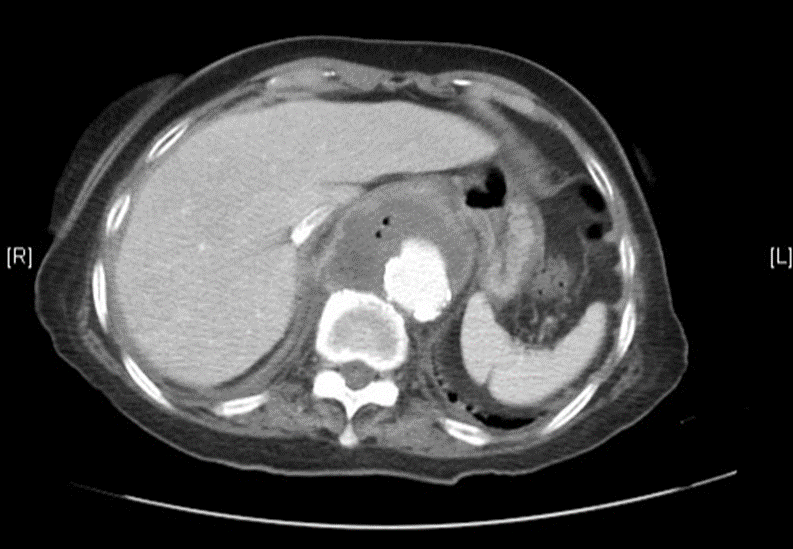

3. Raw egg / Salmonella (aortitis)